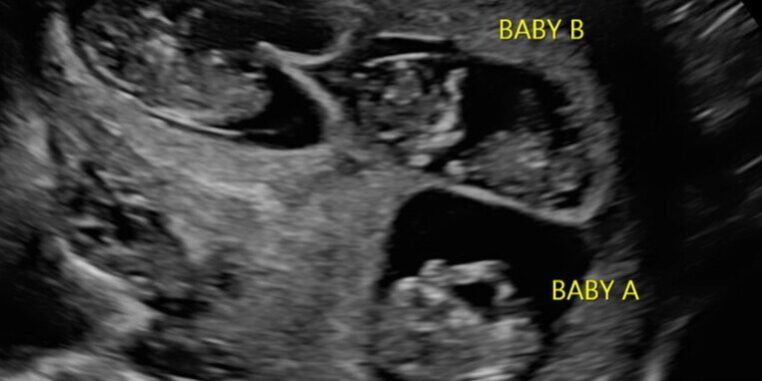

In line with best practices, we generally recommend transferring a single embryo to the surrogate mother. This approach maximizes the chances of a healthy pregnancy while minimizing potential complications. However, it is important to note that all of our surrogate mothers are informed during their recruitment process that they must be understanding of the possibility of carrying identical twins if the transferred embryo happens to split.

While the transfer of one embryo significantly reduces the likelihood of a multiple pregnancy, there remains a rare chance that an embryo will split after implantation, leading to an identical twin pregnancy. As part of our policy, we do not allow for embryo reduction in cases of twin pregnancies. This is a mandatory guideline, reflecting our commitment to protecting the health and integrity of the pregnancy.

Embryo reduction may become necessary in specific circumstances. The most common scenario occurs when two embryos are transferred, and one of them splits, resulting in a triplet pregnancy. Triplet pregnancies carry a heightened risk of preterm labor and other serious complications that can affect both the surrogate mother’s health and the well-being of the babies.